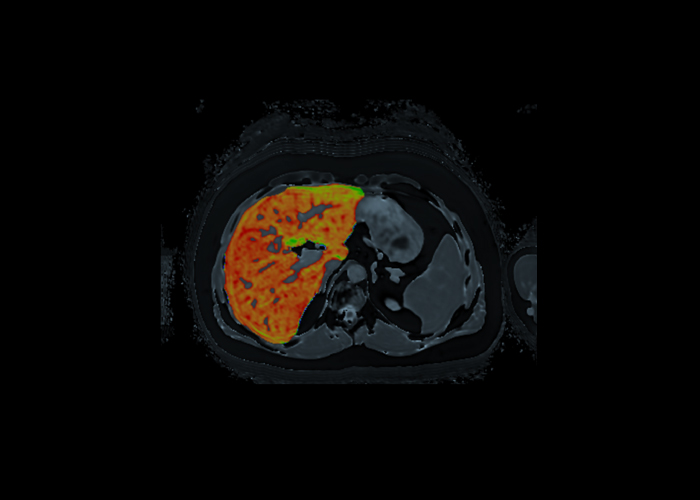

A través de secuencias multi-eco (IDEAL) medimos y cuantificamos la fracción de grasa en el hígado.